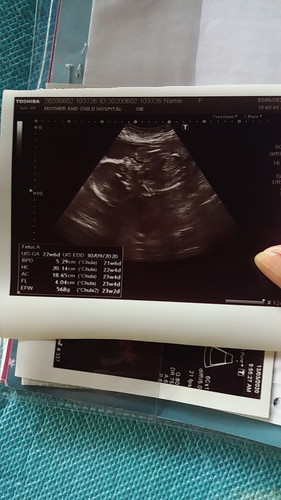

นัดซาวด์ 2 มิ.ย

เมื่อวานไปซาวด์ตามนัดมาแล้วค่ะหลังจากที่รอคอยมานาน ได้ผลออกมาว่าเป็นลูกสาว 80-90% ค่ะได้ยินแค่นี้แม่ก็ยิ้มน้ำตาซึมแล้วค่ะ หลังจากได้ผู้ชายมา 2 คนตอนนี้ คนโต 16 คนเล็ก 13 แล้วค่ะ......แต่หมอยังไม่ฉีดยาบาดทะยักให้เลยค่ะจะ 6 เดือนแล้ว ฉีดแต่ไข้หวัดใหญ่ให้ แม่ๆบ้านไหนได้ฉีดยาอะไรกันบ้างแล้วค่ะ